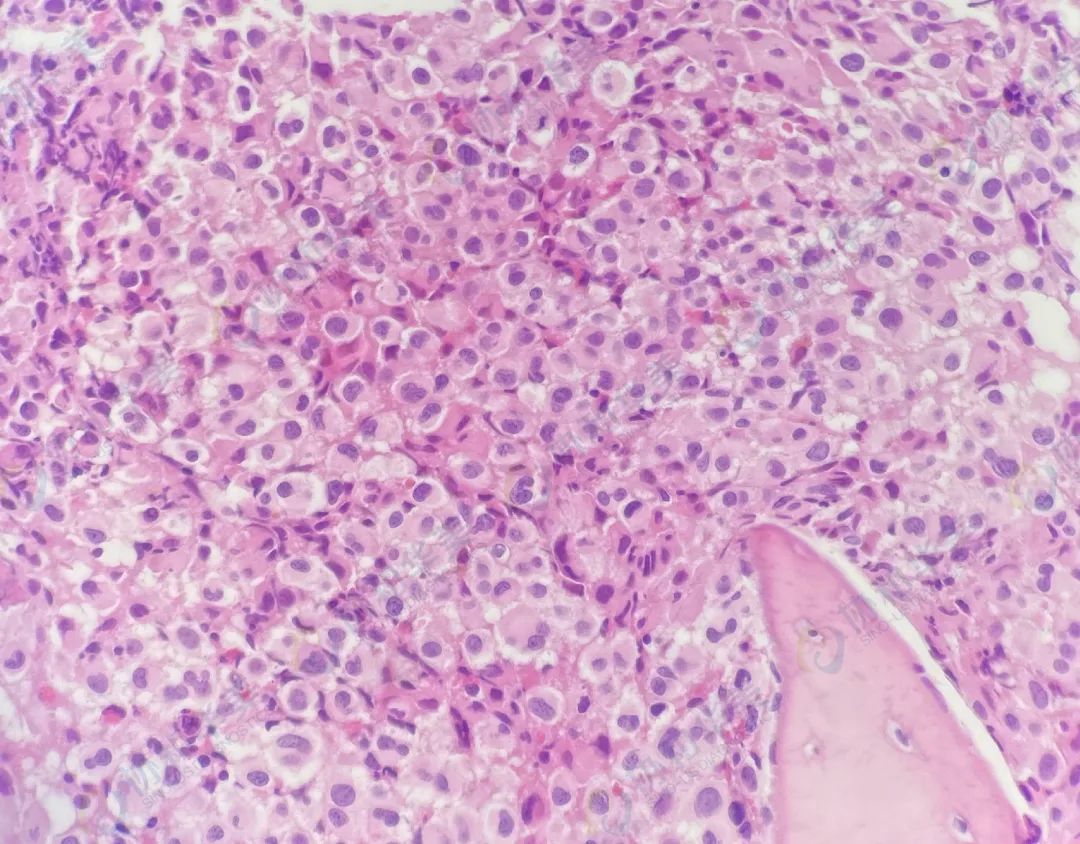

病理切片

HE染色                                           CD138